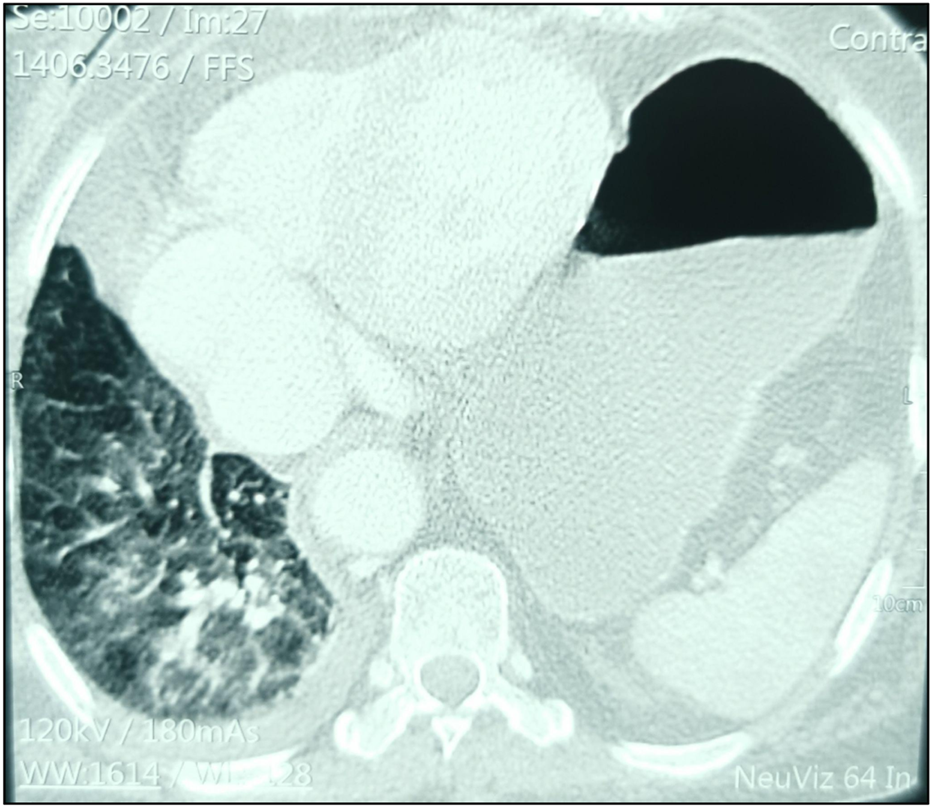

In October 2021, an 88-year-old Black woman presented with a history of hypertension and epigastric pain for 30 years. She had no history of thoracic or abdominal trauma. She was admitted with respiratory distress, constipation, and abdominal pain lasting 24 h. On admission, her Glasgow coma score was 15/15, her oxygen saturation was 89% in ambient air, she had a fever of 38.5 °C, her blood pressure was 110/90 mmHg, her heart rate was 111 beats per minute, her respiratory rate was 32 cycles per minute, and she had a distended, soft abdomen without tenderness (Figure 3A). Paraclinical examinations revealed leukocytosis of 12,000 cells per IU, with neutrophil predominance associated with lymphopenia at 700 cells/IU. The C-Reactive Protein level was 192 mg/L. At this time, it was a unique diagnostic we suspect due to the epidmiology context. Initial investigations included a rapid COVID-19 test, a PCR test for COVID-19, and a chest X-ray. The former two were negative, but the latter showed a gastric pocket in the left chest (Figure 1). We suspected a diaphragmatic hernia. The following day, the patient underwent thoracoabdominal computed tomography, which revealed a left posterolateral diaphragmatic hernia with signs of intestinal necrosis, suggesting strangulation; the PCR test for confirmation of a SARS-CoV-2 infection was negative. Other anomalies seen during the CT scans included the spleen and stomach in the left chest, condensation in the right lung, and right pleural effusion (Figure 2). An electrocardiogram showed sinus tachycardia, and a heart ultrasound showed dextrocardia with a normal left ventricular ejection fraction. Initial resuscitation consisted of hydration with normal saline, insertion of a nasogastric tube, and a Foley catheter. The patient then underwent a mid-laparotomy performed by two senior consultants in general surgery, which revealed a 7-cm left Bochdalek hernia orifice containing the stomach and the spleen which had been accidentally lacerated, and 1 m of necrotic ileum (Figures 3B,C). The herniated contents were returned to the abdominal cavity, the hernia orifice was repaired with interrupted non-absorbable stitches, and a splenectomy and resection of the necrotic ileum with loop stoma formation were performed. The chest and abdomen were drained. The patient was admitted to the intensive care unit (ICU) on mechanical ventilation. She received a course of ceftriaxone (4 g/day) and metronidazole (500 mg/8 h) in addition to other supportive care. She was intubated until the third post-operative day, and on that day, she experienced progressive multiorgan dysfunction, including haematological, renal, and central nervous system dysfunction. She died on the fourth day after the surgery.

FIGURE 2

Chest computed tomography showing the spleen and stomach in the left thoracic cavity and condensation of the right lung associated with the mid-pleura.